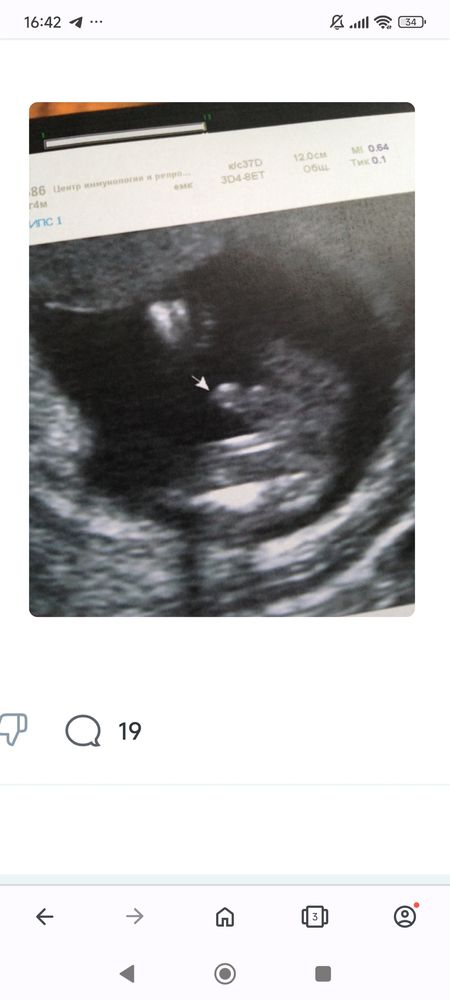

Эва , Изображениевот 16 недель 😁